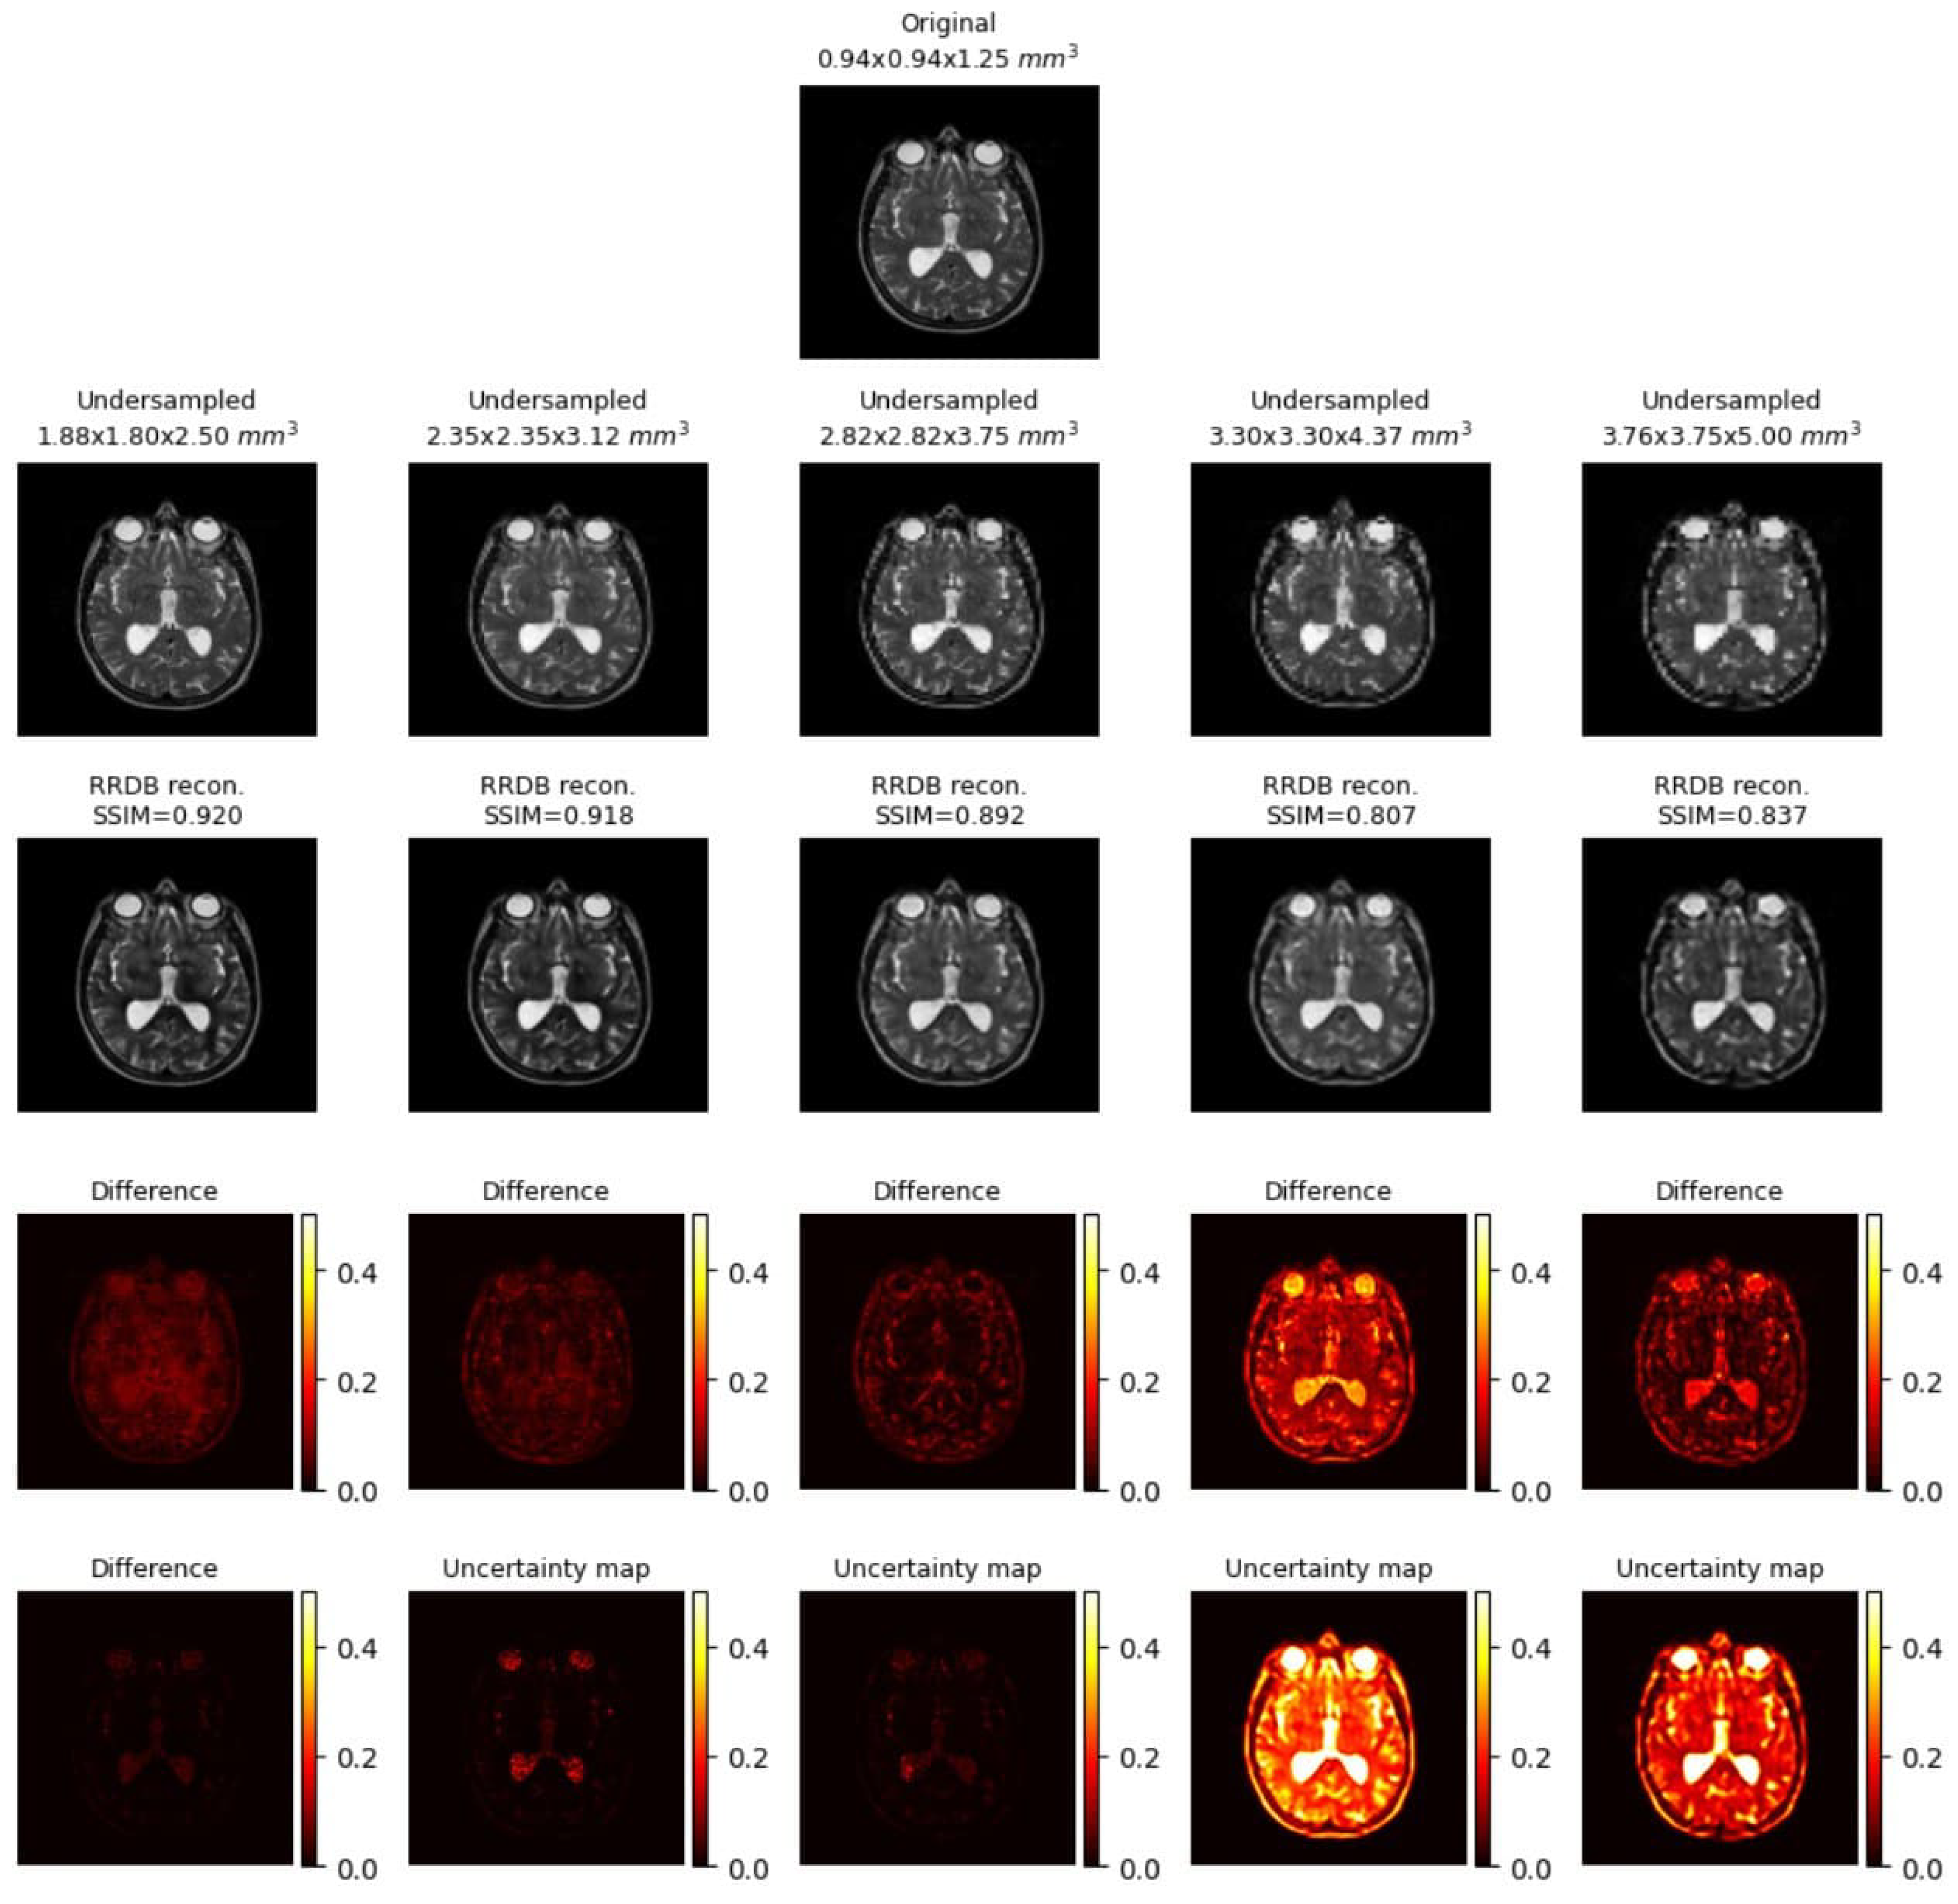

Uncertainty Mapping

2.4. Uncertainty Mapping

Uncertainty Mapping Pipeline

- 1.

- Iteratively, model predictions are generated from low-resolution images using the trained model weight but with different dropout rates and Gaussian noise in the intermediate layers.

- 2.

- Compile all the generated images.

- 3.

- The uncertainty map is the pixel-wise variance across all these generated images.